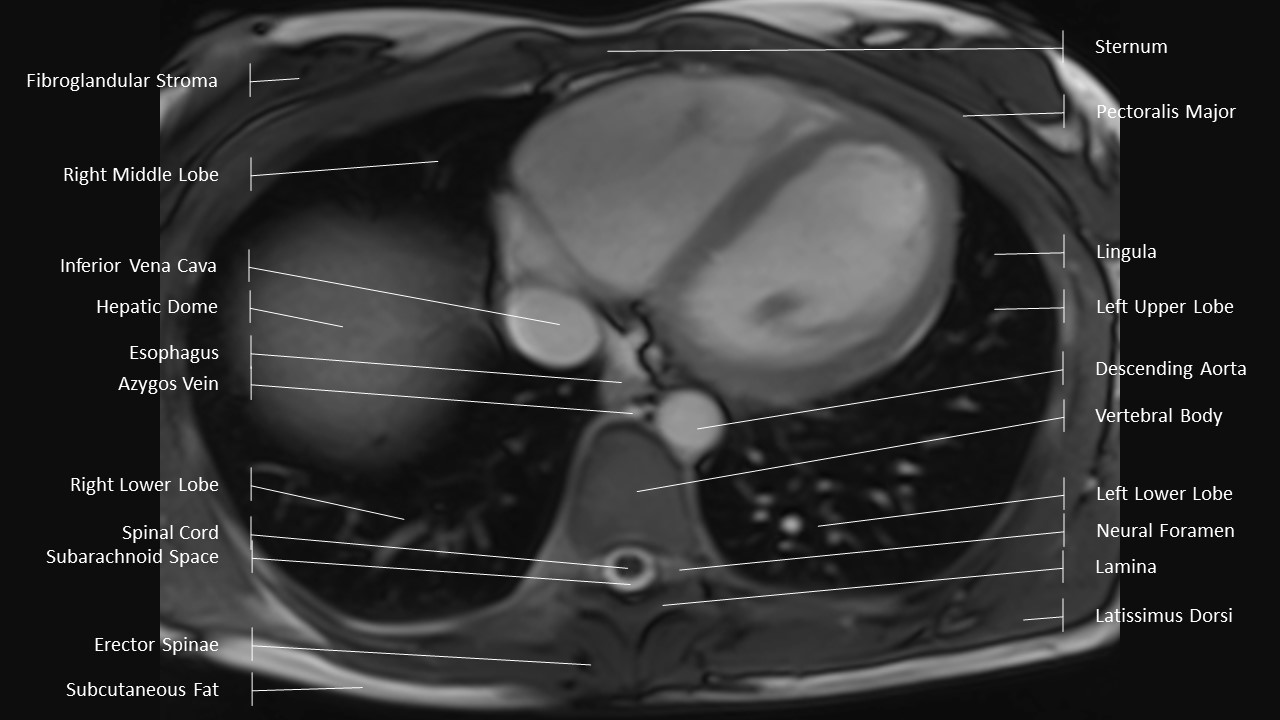

Axial Series